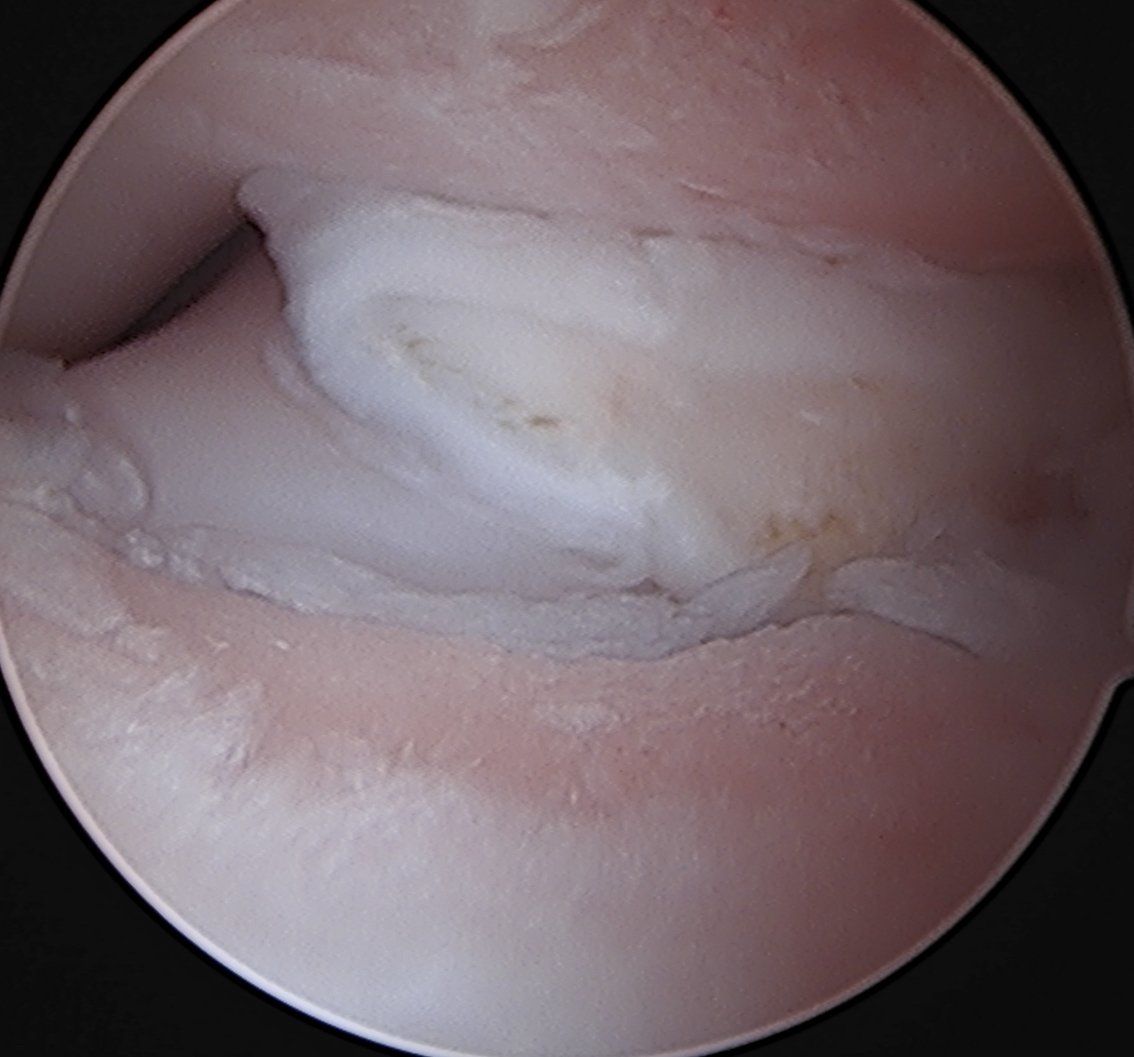

L'arthroscopie des deux coudes, réalisée sur la même anesthésie générale, a mis en évidence une lésion du processus coronoide médiale à droite comme à gauche, et surtout une érosion majeure et avancée du cartilage du compartiment médial. Cette atteinte est caractéristique d'une maladie du compartiment médial du coude, composante de la dysplasie du coude chez le chien. Le traitement sous arthroscopie consiste à tout d'abord réaliser un bilan lésionnel complet de la surface articulaire. Ensuite, si un fragment est présent, cette technique chirurgicale minimallement invasive permet de le retirer. Par ailleurs, une ostéotomie du processus coronoide médial peut également être réalisée sous contrôle visuel direct. Le pronostic après une arthroscopie du coude est bon dans la majorité des cas. Certains patients peuvent présenter une gène clinique et une boiterie au long terme en fonction du développement de lésions d'arthrose. Après le retrait du fragment dans le coude, cette articulation reste néanmoins abimée et nécessite par la suite une prise en charge de l'arthrose au long cours. L'arthroscopie permet donc à la fois de réaliser un bilan lésionnel complet de l'articulation, mais également de traiter la lésion lorsqu'il s'agit d'un fragment dans l'articulation.

Seule l'arthroscopie peut permettre d'orienter le propriétaire sur un pronostic et sur l'évolution arthrosique de son animal.

Légendes :

Images arthroscopiques du coude. L'incisure ulnaire (image 1) est normale. Un fragment détaché dans l'articulation est visible, associée à une lésion majeure de la surface articulaire sur l'image 2. L'image 3 montre le retrait du fragment à l'aide d'une pince. L'image 4 met en évidence une lésion d'OCD du condyle huméral médial et les lésions cartilagineuses associées.